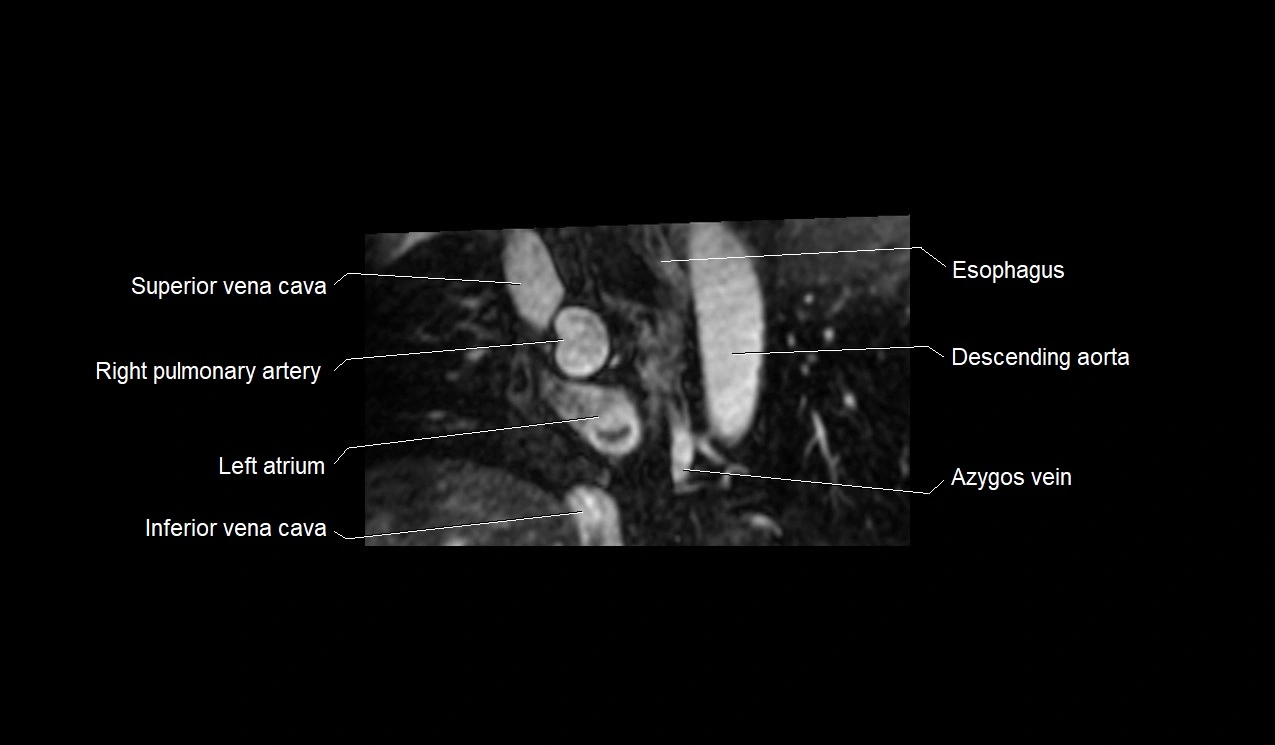

- Superior vena cava

- Azygos vein

- Inferior vena cava

- Left atrium

- Right pulmonary artery